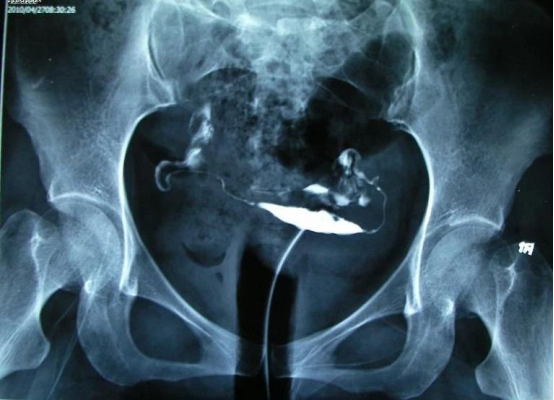

造影片可以看到一侧或双侧输卵管伞端有造影剂溢出,盆腔有造影剂涂抹。术后积极试孕,这一般没有争议。

输卵管通畅